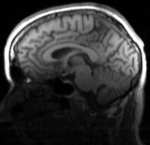

RegLib C32 registered.gif T1 registered to DTI Affine + BSpline (click to enlarge)